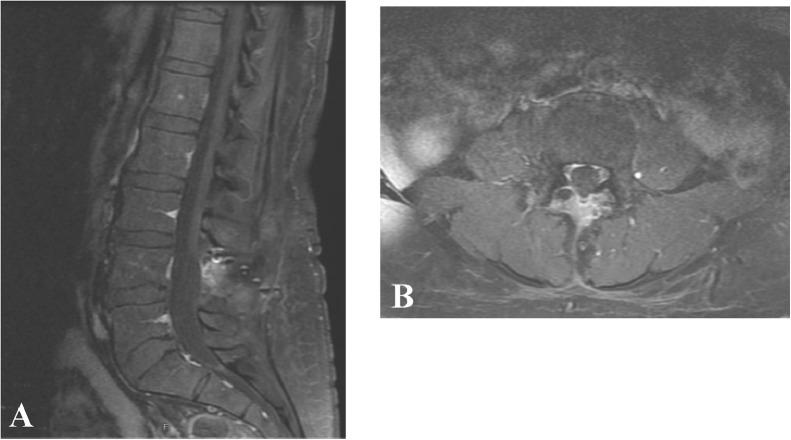

Solitary fibrous tumor in the lumbar spine is a rare pathology with non-specific radiographic features, sometimes resulting in misdiagnosis. Our patient was a 41-year old female who presented with low back pain and bilateral leg pain. Initial MRI showed a lesion misdiagnosed for a sequestered disc at the mid L4-5 level, which was subsequently characterized appropriately and treated surgically, with resolution of symptoms. Pathologic diagnosis was most consistent with a solitary fibrous tumor due to STAT 6 and CD 34 reactivity. Long-term follow up is recommended in these patients to monitor tumor recurrence and evidence of metastasis.

摘要

腰椎孤立性纤维瘤是一种罕见的病理类型,具有非特异性的影像学特征,有时会导致误诊。我们的患者是一名41岁女性,表现为腰痛和双侧腿痛。最初的MRI显示L4 - 5水平中部有一个病变,被误诊为游离椎间盘,随后该病变得到了正确诊断并接受了手术治疗,症状得以缓解。病理诊断由于STAT 6和CD 34反应性,最符合孤立性纤维瘤。建议对这些患者进行长期随访,以监测肿瘤复发和转移迹象。